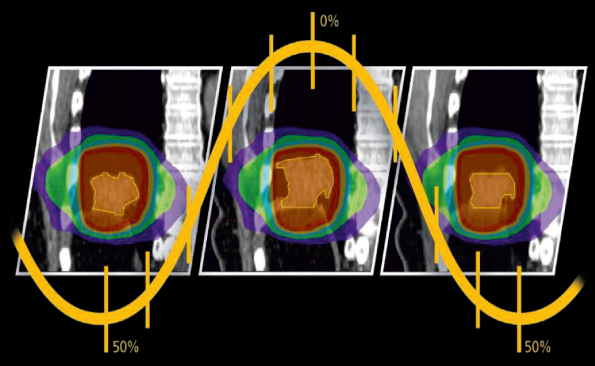

4D Binning

Tüm 4D işleme çalışmaları tek bir sistemde yapılabilir.

MIM Maestro’nun 4D binning özelliği, faz tabanlı ve genlik tabanlı binning işlerini otomatik yapabilir, böylece veri alma çalışma istasyonlarına duyulan gereksinim azalır. Otomatik kontur yayma özelliği, bir kapılı fazda yapılan konturlama işleminin bir dakikadan az bir sürede tüm kapılı fazlara deforme edilmesini sağlar. Sonra her bir kapılı fazda bulunan konturlar, tek bir tıklama ile klinik açıdan uygun bir ITV’ye dönüştürülebilir.

Söz konusu ITV, hastanın solunum saykılındaki farklı fazlar sırasında tümörün hareket alanının tamamını doğru şekilde gösterir. PET/CT, MR v e doz aynı anda tek bir faza, maksimum IP/ortalama IP veya cine’ye hizalanabilir.